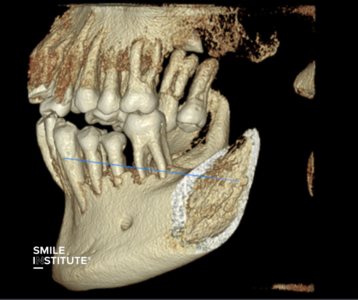

Amikor egy páciens fogászati problémával érkezik, az első és legfontosabb lépés a pontos diagnózis felállítása. A hagyományos panorámaröntgen ugyan sok esetben megfelelő információt nyújt, de vannak helyzetek, amikor ez nem elegendő. A fogászati CT (CBCT – Cone Beam Computed Tomography) lehetővé teszi, hogy a fogorvos háromdimenziós képet kapjon a teljes állcsont szerkezetéről, beleértve a rejtett problémákat is, amelyeket egy hagyományos röntgen nem tud kimutatni.

A kis fogászati röntgen (intraorális felvétel) részletesebb képet ad egy-egy fogról, így kiválóan alkalmas a szuvasodások vagy gyökérkezelési problémák feltárására. A fogászati CT (CBCT) pedig háromdimenziós képet biztosít az állcsont és a fogak szerkezetéről, így komplexebb beavatkozások előtt – például implantátum vagy szájsebészeti műtétek esetén – elengedhetetlen.

A fogászati CT egyedülálló részletességgel mutatja meg az állkapocs és a fogak szerkezetét, amely számos területen kulcsfontosságú:

➜ Fogászati implantáció esetén: A beültetendő implantátum helyének pontos meghatározása elengedhetetlen a sikeres beavatkozáshoz. A CT-felvétel segít feltérképezni a csontállomány sűrűségét és térfogatát, így az implantátum biztonságosan és megfelelő pozícióba kerülhet.

➜ Foghúzás és bölcsességfog eltávolítás esetén: A komplikált fogeltávolítások során a CT segít meghatározni az idegek és az érintett fogak pontos helyzetét, elkerülve a szövődményeket.

➜ Rejtett problémák feltárása esetén: Olyan elváltozásokat is kimutathat, amelyeket egy hagyományos röntgen nem, például cisztákat, daganatokat vagy rejtett gyulladásokat.